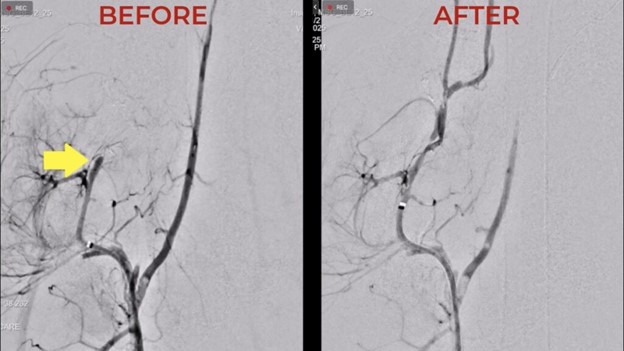

In the transatlantic procedure, a neurosurgeon, based in Arizona, remotely aspirated blood clots placed in the extracranial arteries of the study animal at Inselspital in Bern, more than 9,000 km away. The procedures were executed with real-time remote control and visual guidance provided by X-ray and camera systems. The teleoperation was conducted over a secure public internet connection, demonstrating reliable performance.

In a separate intra-Switzerland procedure, Dr. Tilman Schubert, Senior Physician, Interventional Neuroradiology at the University Hospital of Zurich, successfully aspirated a clot placed in the right infraorbital artery of the animal model at Inselspital in Bern, while Dr. Tomas Dobrocky, Attending Physician Neuroradiology from Inselspital Department of Neurology oversaw the procedure at the bedside.

“In the study, we achieved accurate navigation and clot removal in a live model in an intra-Switzerland hospital-to-hospital teleoperation,” said Dr. Schubert. “This proves the technical feasibility of remote neuro-interventions”.